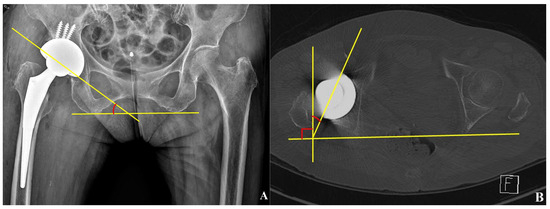

2.4. Cup Position and Fixation

2.5. 2D-Based Measurement of Host Bone Coverage from Plain Radiographs of the Pelvis

2.6. 3D-Based Measurement of Host Bone Coverage from CT Scans